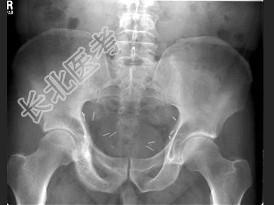

- 单项选择题男,56岁, 右髋部疼痛,5年前被确诊为前列腺癌, 结合图像,最可能的诊断是 ( )

A、骨纤维异常增殖症

B、转移性骨肿瘤

C、畸形性骨炎

D、内生软骨瘤

E、非骨化性纤维瘤